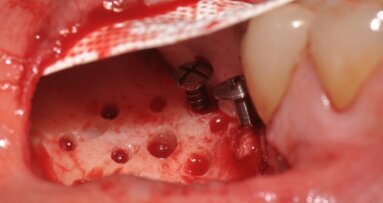

La tecnica è indicata per elementi dentali da estrarre mesio inclinati o elementi di ponte, che presentino un deficit orizzontale della cresta ossea a fianco dell’elemento da estrarre. Il protocollo operativo prevede, dopo l’estrazione, una incisione in cresta fino al dente contiguo e intrasulculare per mezzo dente sia vestibolare che buccale-palatale, se necessario. Si procede poi scollando ed evidenziando la parte ossea dove dovremo posizionare la membrana e il biomateriale, senza eccedere poiché lo scollamento minimo ci garantirà la stabilità dell’innesto. Raggiunte le pareti che riprendono uno spessore osseo morfologicamente normale si interrompe lo scollamento e si imbusta una membrana in collagene precedentemente tagliata e bagnata con la colla di fibrina, in modo che si incolli al lembo vestibolare. A questo punto il biomaterale miscelato con la colla di fibrina (Sticky Bone) viene imbustato poco per volta iniziando dall’alveolo e poi all’interno del sito creato dallo scollamento, senza necessità di fori nella corticale (Figg. 2a, 3a, 4a, 5, 6a). La rigenerazione viene guidata dai tessuti che ci indicheranno quanto materiale poter inserire, non effettuando scarichi verticali è il lembo stesso a essere contenitivo e a dare stabilità all’innesto. Il lembo viene suturato a punti staccati singoli ottenendo una chiusura per prima intenzione senza dover incidere il periostio (Figg. 1a, 2a, 3a, 6a); mentre nella zona dell’alveolo, in cui gli strati di membrana possono essere aumentati, la sutura sarà incrociata e la guarigione per seconda intenzione. Ovviamente se dovessimo trovarci in difficoltà potremo creare un rilascio periostale, ponendo sempre attenzione a non far venire meno quella capacità contenitiva del lembo che è alla base di questa tecnica. Nei casi presentati il rilascio periostale non è stato eseguito, iniziare il lembo con un incisione bisellata in cresta può essere d’aiuto a evitare il rilascio periostale (Fig. 2a).

Fig. 1a_Estrazione di radice distale di 46 e innesto su deficit di 45 e 46.

Fig. 4a_Elemento 36 mesio inclinato, deficit orizzontale in zona 35 risolto con tecnica S.A.T.